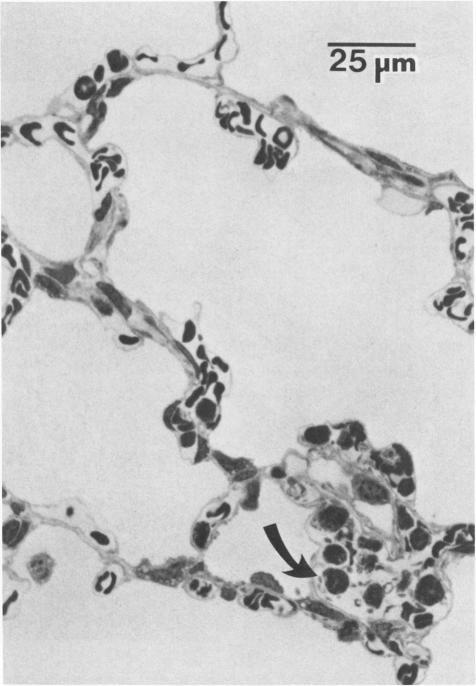

Acetyl glyceryl ether phosphorylcholine (AGEPC; 1-O-hexadecyl-2-acetyl-sn-glyceryl-3-phosphorylcholine) was infused intravenously into rabbits (0.5 micrograms/kg); subsequently, temporal pulmonary alterations were assessed histologically. Within 30 seconds after AGEPC infusion, widespread platelet and neutrophil aggregates were distributed throughout the pulmonary microvasculature. Concomitantly, small muscular arteries and bronchioles throughout the lungs were contracted. Five minutes after AGEPC infusion, intravascular pulmonary platelet aggregates were less frequent and smaller than those observed at 30 seconds after infusion; however, AGEPC-induced pulmonary neutrophil sequestration persisted. Moreover, at this time, large mononucleated cells and damaged endothelial cells were prevalent throughout the pulmonary microvasculature. Sixty minutes after infusion, neither platelet aggregates nor arterial or bronchiolar constriction was observed. However, in most animals, neutrophils and large mononucleated cells were still abundant, and focal endothelial cell alterations persisted. In addition, discrete areas of interstitial hemorrhage around small and medium-sized arteries were present. These studies suggest that the intravascular release of AGEPC could initiate significant pulmonary injury and therefore could be an important etiologic factor in the development of inflammatory lung diseases.

将乙酰甘油醚磷酸胆碱(AGEPC;1-O-十六烷基-2-乙酰基-sn-甘油-3-磷酸胆碱)以0.5微克/千克的剂量静脉注射到兔子体内;随后,通过组织学评估肺部随时间的变化。在注入AGEPC后30秒内,广泛的血小板和中性粒细胞聚集体分布在整个肺微血管系统中。与此同时,肺部各处的小肌性动脉和细支气管收缩。注入AGEPC后5分钟,血管内肺血小板聚集体比注入后30秒时更不频繁且更小;然而,AGEPC诱导的肺中性粒细胞滞留持续存在。此外,此时,大单核细胞和受损内皮细胞在整个肺微血管系统中普遍存在。注入后60分钟,未观察到血小板聚集体或动脉或细支气管收缩。然而,在大多数动物中,中性粒细胞和大单核细胞仍然大量存在,局部内皮细胞改变持续存在。此外,在中小动脉周围存在离散的间质出血区域。这些研究表明,AGEPC的血管内释放可引发严重的肺损伤,因此可能是炎症性肺病发展的重要病因。